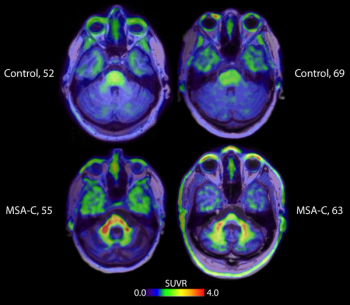

Emerging research suggests that an experimental alpha-synuclein (a-syn) positron emission tomography (PET) tracer may help diagnose multiple system atrophy (MSA) and potentially other neurodegenerative diseases such as Parkinson’s disease and Lewy body dementia.